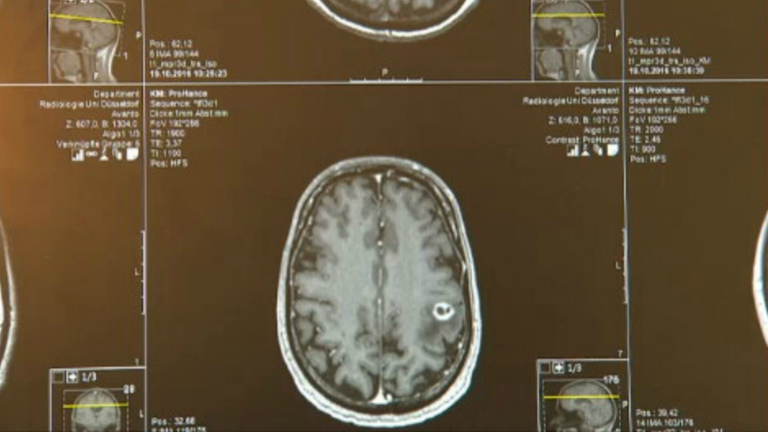

Durch die Op schwillte mein Hirn an und ich musste eine sehr hohe Dosis an Cortison nehmen. Erholung nach Hirn OP Operation von Hirntumoren DKG - Krebsgesellschaf Normalerweise erfolgt eine MR- oder CT-Kontrolle am nächsten Tag oder spätestens 48 Stunden nach der Operation um das Ergebnis der Operation festzustellen. Eine Reha nach einer Hirn OP ist in jedem Fall zu empfehlen.